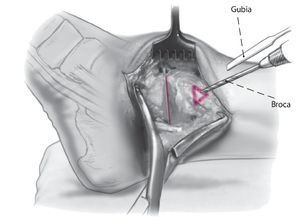

La técnica quirúrgica se ilustra en las figs. 1-13.

Fig. 10 Utilice la broca de 2,5 mm y un gubia de 1 cm para extraer un triángulo de capa cortical en el lado anteromedial de la tibia. La base del triángulo debe ser paralela a la planta del pie. Eso permite el avellanado, así como un posicionamiento más pendiente del tornillo respecto a la tibia.

Fig. 11 Mediante el uso de una broca de deslizamiento/broca guía de 4,5 mm se realizan agujeros en sentido medial y lateral, seguidos de agujeros de 3,2 mm con rosca en la capa cortical opuesta. Se colocan dos tornillos corticales de fijación de 4,5 mm con rosca completa y arandelas. El tornillo medial se dirige un poco en dirección anterior, mientras que el tornillo lateral se orienta ligeramente más posterior. Lo ideal es que el tornillo cruce craneal al nivel de la osteotomía.